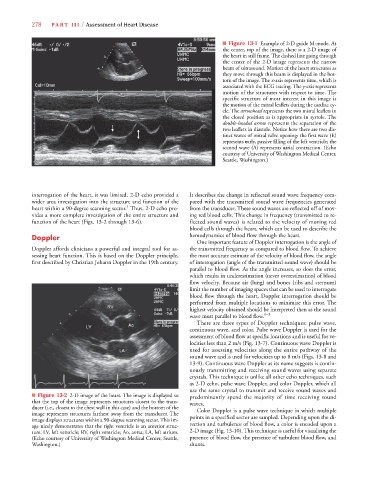

■ Figure 13-1 Example of 2-D guide M-mode. At

the center, top of the image, there is a 2-D image of

the heart in still frame. The dashed line going through

the center of the 2-D image represents the narrow

beam of ultrasound. Motion of the heart structures as

they move through this beam is displayed in the bot-

tom of the image. The x-axis represents time, which isx x

associated with the ECG tracing. The y-axis represents

motion of the structures with respect to time. The

specific structure of most interest in this image is

the motion of the mitral leaflets during the cardiac cy-

cle. The arrowhead represents the two mitral leaflets in

the closed position as is appropriate in systole. The

double-headed arrow represents the separation of the

two leaflets in diastole. Notice how there are two dis-

tinct waves of mitral valve opening: the first wave (E)

represents early, passive filling of the left ventricle; the

second wave (A) represents atrial contraction. (Echo

courtesy of University of Washington Medical Center,

Seattle, Washington.)